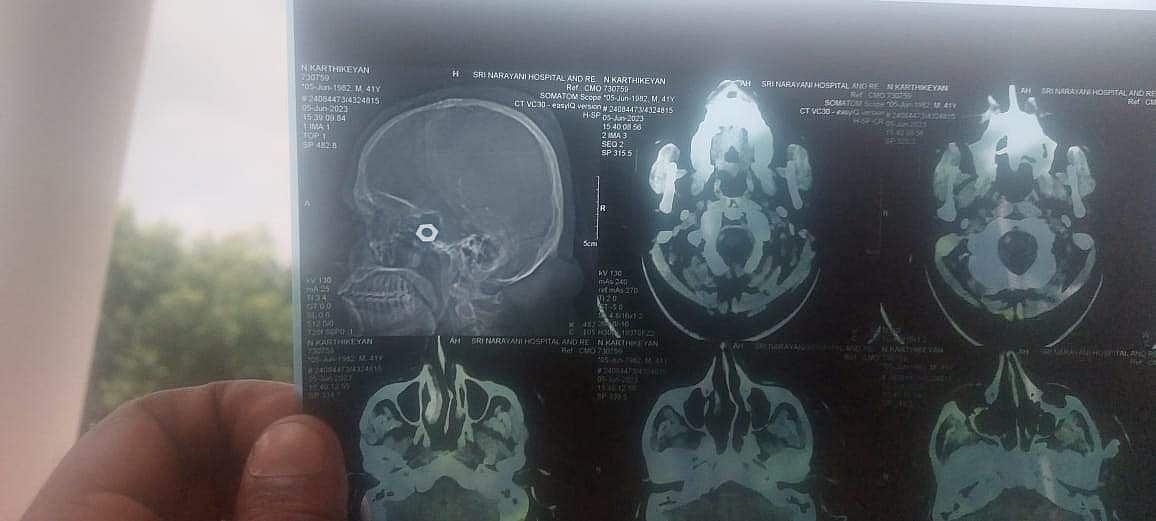

இதனால், அதிருப்தியடைந்த உறவினர்கள் கார்த்திகேயனை அங்கிருந்து டிஸ்சார்ஜ் செய்து வேலூரில் உள்ள தனியார் மருத்துவமனையில் அனுமதித்தனர். அங்கு மருத்துவர்கள் ஸ்கேன் செய்ததில் கார்த்திகேயனின் தலையில் தையல் போடப்பட்ட இடத்தில் இரும்பு ‘போல்ட்டு’ ஒன்று இருப்தைப் பார்த்து அதிர்ச்சியடைந்தனர். பின்னர், தையல் பிரிக்கப்பட்டு அந்த இரும்பு நட்டை அகற்றியுள்ளனர். தொற்று காரணமாக அவருக்கு இரண்டு நாள் கழித்தே மீண்டும் அந்த இடத்தில் தையல் போட முடியும் என்று மருத்துவர்கள் கூறியுள்ளனர்.